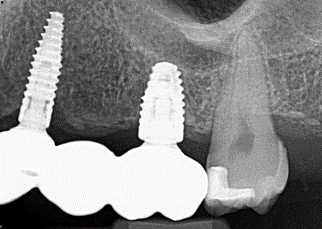

12. (Select ONE OR MORE correct answers.)

Tooth 4.8 is planned for extraction. Which radiographic findings suggest an increase in the degree of difficulty of the extraction?